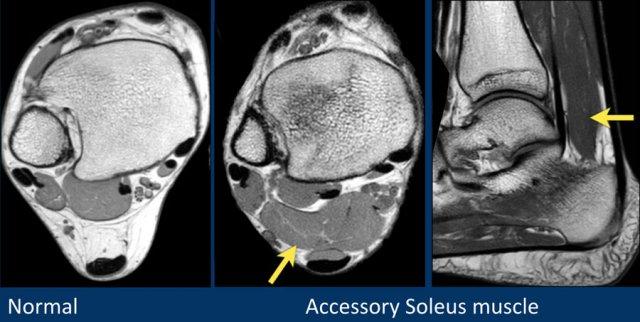

Gân

Giải phẫu trên mặt phẳng cắt ngang

Các gân có thể được chia thành bốn khoang:

- Khoang trong (từ trong ra ngoài: Tom-Dick-Harry)

- Gân cơ chày sau (Tibialis Posterior – PTT)

- Gân cơ gấp các ngón chân dài (Flexor Digitorum)

- Gân cơ gấp ngón cái dài (Flexor Hallucis Longus)

- Khoang sau

- Gân Achilles

- Gân cơ gan chân (Plantaris)

- Khoang ngoài

- Gân cơ mác dài (Peroneus Longus)

- Gân cơ mác ngắn (Peroneus Brevis)

- Khoang trước (từ trong ra ngoài: Tom-Hates-Dick)

- Gân cơ chày trước (Tibialis Anterior)

- Gân cơ duỗi ngón cái dài (Extensor Hallucis Longus)

- Gân cơ duỗi các ngón chân dài (Extensor Digitorum)